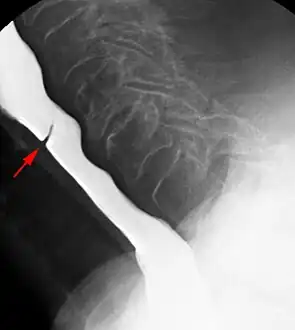

Esophageal web

Esophageal webs are thin membranes occurring anywhere along the esophagus.[1]

Esophageal webs are thin 2–3 mm (0.08–0.12 in) membranes of normal esophageal tissue consisting of mucosa and submucosa that can partially protrude/obstruct the esophagus. They can be congenital or acquired. Congenital webs commonly appear in the middle and inferior third of the esophagus, and they are more likely to be circumferential with a central or eccentric orifice. Acquired webs are much more common than congenital webs and typically appear in the cervical area (postcricoid).

The diagnostic test of choice is a barium swallow.